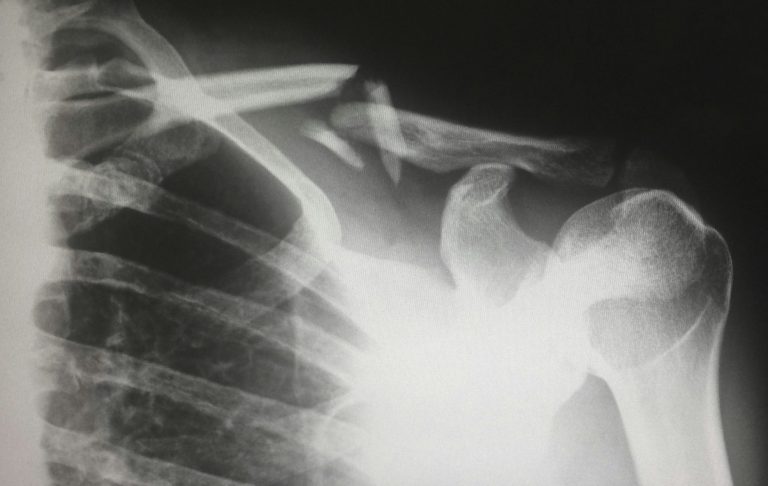

Allvarligare skador vid vandring – när marginalerna försvinner

Allvarligare skador som benbrott och kraftiga fallskador är betydligt ovanligare än skavsår och stukningar – men de förekommer, särskilt i blockterräng, på hala spångar eller vid snedtramp där ryggsäcken skapar obalans.

Ett ben kan till exempel fastna mellan stockar eller stenblock samtidigt som kroppen och packningen fortsätter i en annan riktning. Resultatet kan bli allvarliga skador som snabbt kräver avbruten tur och extern hjälp.

Vid misstänkt benbrott eller allvarlig fallskada:

- Försök inte belasta den skadade kroppsdelen

- Stabiliserar så gott det går med förband, kläder eller tillgänglig utrustning

- Håll den skadade varm

- Tillkalla hjälp och avbryt vandringen

Benbrott är en av anledningarna till att ruttval, tempo och säkerhetsmarginaler är minst lika viktiga som utrustning vid vandring.